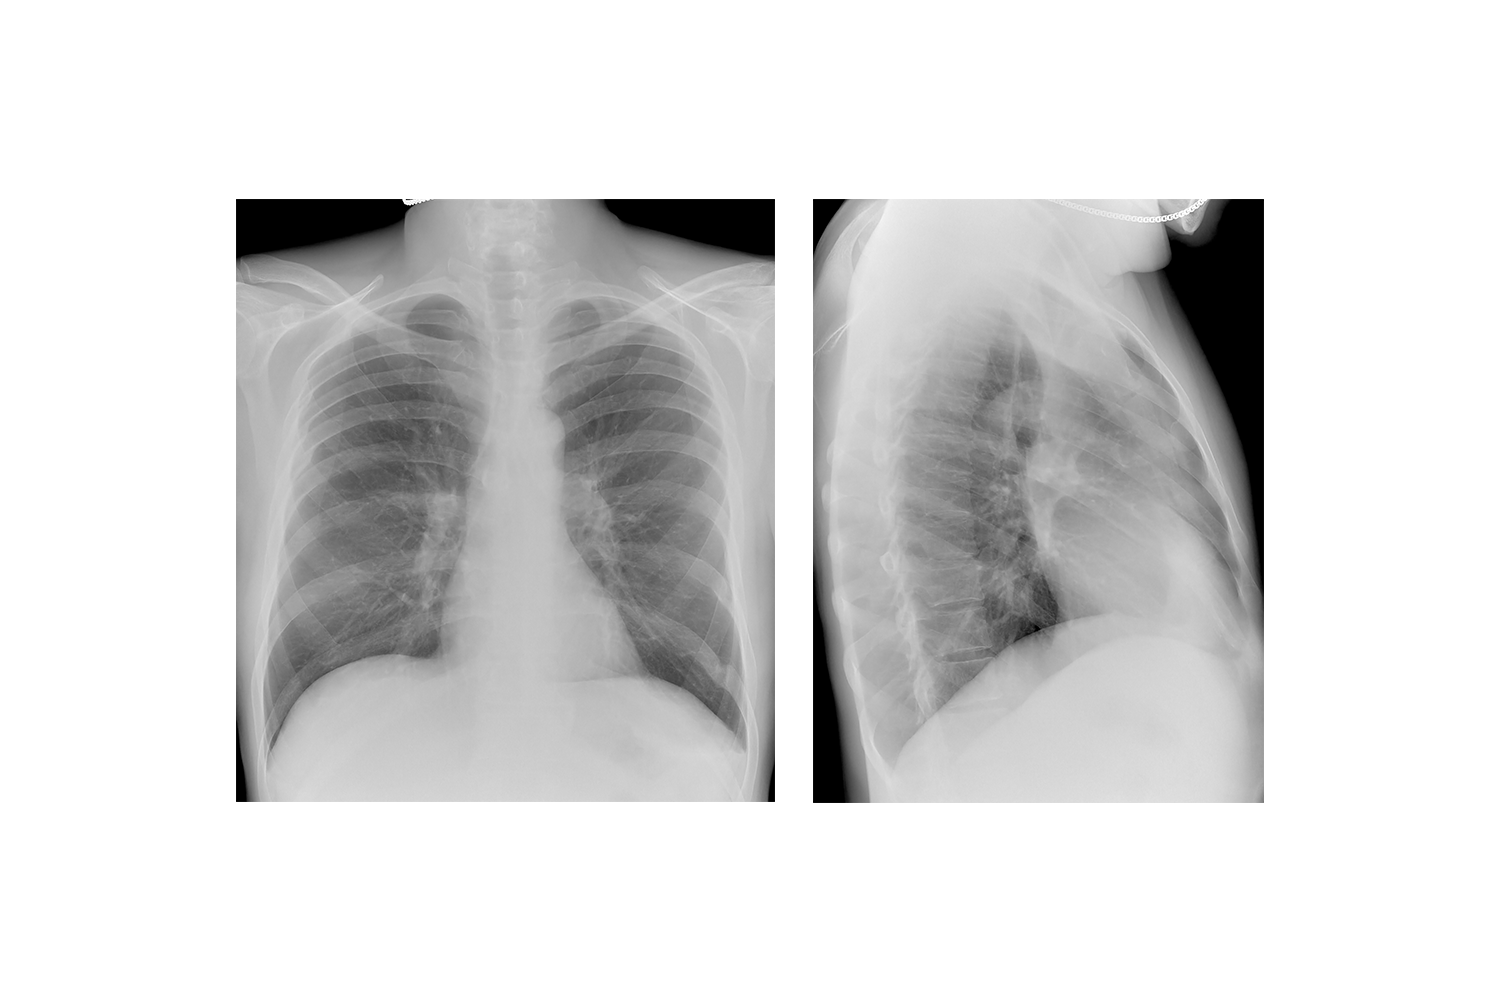

Изучение дозы излучения при рентгеновских исследованиях: визуализация